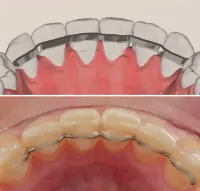

Arco Linguale

Dispositivo ortodontico indicato per mantenere gli spazi di eruzione in pazienti in fase di permuta della dentatura. Realizzato con tecnologia CAD-CAM, garantisce precisione unica e comfort ottimale per il paziente.